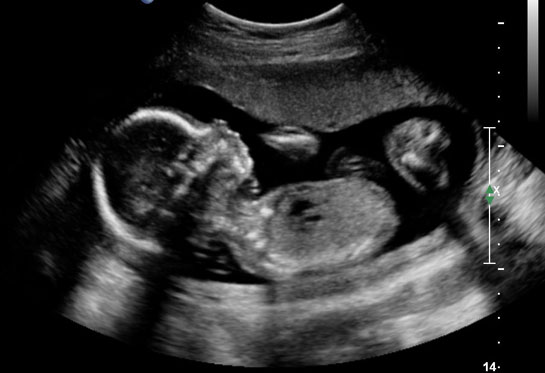

| 36 haftalık gebelik, bir hamilelik sürecinin önemli bir aşamasını temsil eder. Bu dönem, fetüsün gelişiminde kritik bir dönemdir ve anne adayının sağlığı bakımından da dikkate alınması gereken birçok faktör vardır. Bu makalede, 36 haftalık gebelik sürecinin özellikleri, anne adayı ve fetüs üzerindeki etkileri ile birlikte, bu dönemde dikkat edilmesi gereken konular ele alınacaktır. Fetüs Gelişimi 36 haftalık gebelikte fetüs, doğuma oldukça yakın bir dönemde bulunmaktadır. Bu aşamada fetüsün gelişimi ile ilgili bazı önemli noktalar şunlardır:

36 haftalık gebelik sürecinde yaşadıklarım gerçekten çok ilginç. Bebeğimin boyunun 47 cm ve ağırlığının 2 kg 700 gram olması beni heyecanlandırıyor. Her gün ortalama 30 gram alması da bu süreçteki gelişimini gösteriyor. Bebeğin doğuma hazırlandığını bilmek güzel ama bu haftayı atlatmanın verdiği rahatlıkla birlikte üzerimdeki yükün biraz hafiflemesi de sevindirici. Hormonal değişimler nedeniyle bedenimdeki gevşeme ve yumuşama beni yavaşlatıyor. Yürüyüşlerim değişti, bu da normal. Ancak bel ve pelvisteki ağrılar beni rahatsız ediyor. Yemek yeme konusunda da sıkıntılar yaşıyorum, bebeğim artık çok yer kaplıyor. Küçük porsiyonlarla beslenmek zorundayım. Mide yanmamın hafiflemesi, nefes almamı kolaylaştırdı ama bebeğim aşağı doğru inmeye çalıştıkça alt karın bölgesinde baskı hissediyorum, bu da rahatsız edici. Braxton Hicks kasılmalarının daha fazla hissedilmesi de dikkatimi çekiyor. Doğum sancılarının başlaması için her an hazırlıklı olmam gerektiğini biliyorum. Bebeğimin hareketlerinde azalma olursa ya da vajinal kanama yaşarsam hemen doktora gitmem gerektiğini unutmayacağım. Vajinal akıntıdaki artış beni endişelendiriyor ama cinsel birliktelikten sonra lekelenmenin normal olduğunu öğrenmek biraz olsun rahatlatıyor. Karın kaşıntım da dayanılmaz hale geldi; badem yağı ve E vitamini kremleri kullanmaya başladım. Uyku sorunlarıyla başa çıkmak için rahat kıyafetler giymek zorundayım. Ayaklarımda ve bileklerimdeki şişlik beni oldukça rahatsız ediyor fakat bol sıvı tüketmeye dikkat ediyorum. Halsizlik hissi normal ama doğumun yaklaşmasıyla birlikte bir enerji patlaması yaşıyorum. Artık tuvalet ihtiyacım da arttı, bu durum da yeni bir alışkanlık haline geldi. Tüm bu süreç gerçekten hem zorlu hem de heyecan verici!